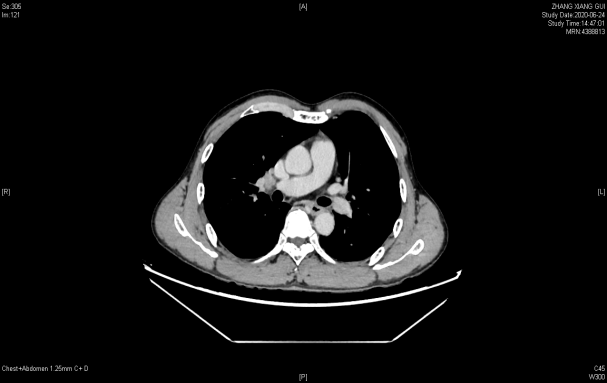

联合治疗2周后胸部增强CT:食管中段管壁增厚,增强扫描呈较明显不均匀强化,较前好转,胸廓入口水平气管右侧见肿大淋巴结,明显不均匀强化,较前减小。

2020年6月24日 联合治疗2周期后胃镜(上)和胸部增强CT(下)